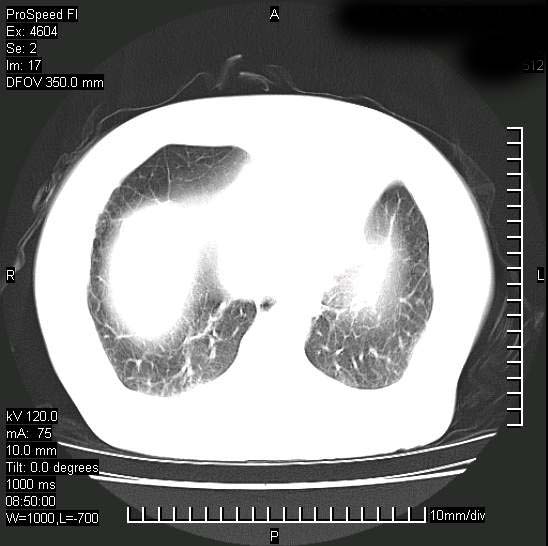

十几年前曾患肺结核,一周前突咳血约100ml,中性粒细胞稍高,诊断两上肺陈旧结核,下肺炎症,给予抗炎治疗,近几日晚上高热,39度,仍咳少量血,4天前ct及今天ct上传。

[face=黑体]8月30日[/face]

支持陈旧性肺结核并两下肺感染,两侧胸腔积液。

考虑1双肺tb灶;右下肺支气管壁增后,建议除外占位 3双侧胸腔积液,

短短几天内,病变范围明显增多扩大,以左侧明显,而且双侧出现胸水,还是考虑感染.

支持  结核ban感染,节段性肺不张,支气管内膜结核可能

继发性结核感染加重。左侧合并有支气管内膜结核。

1)两肺结核并感染。2)不排除左肺上叶中央型肺癌并阻塞性肺炎、肺不张可能;建议行纤支镜检查。3)右肺门及纵隔淋巴结肿大。4)双侧胸腔积液。

陈旧性肺结核及左下肺不张,咯血后肺部感染,双胸腔积液,高热可能与痰液引流不畅有关。